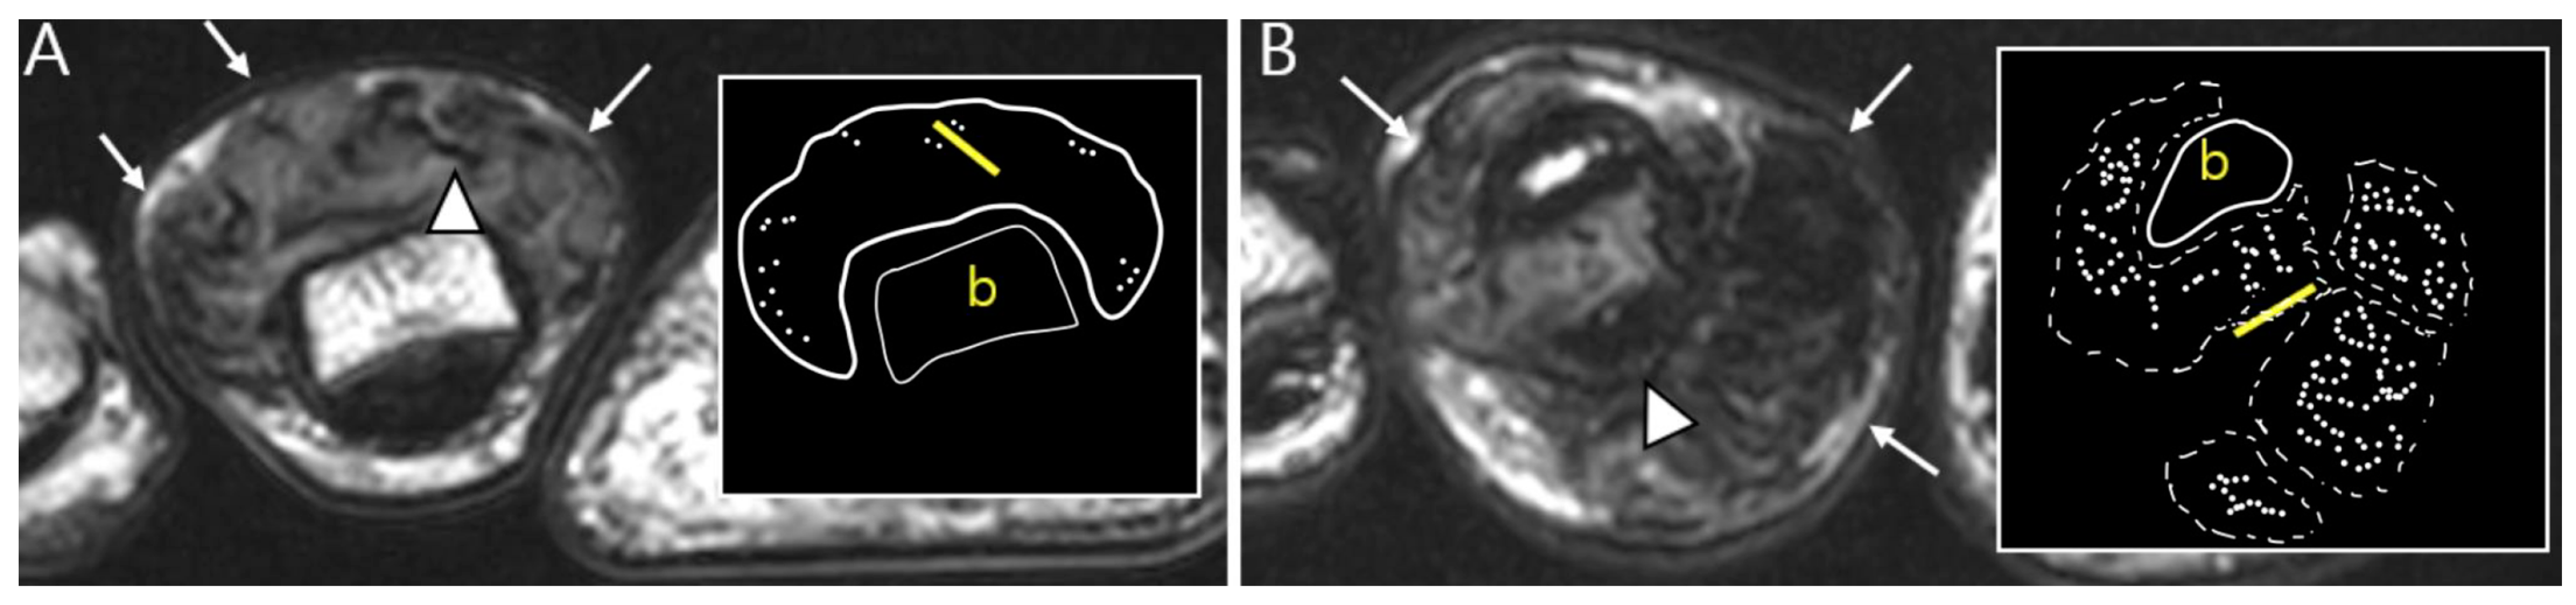

2.5. Advanced MRI Sequences for D-TSGCT